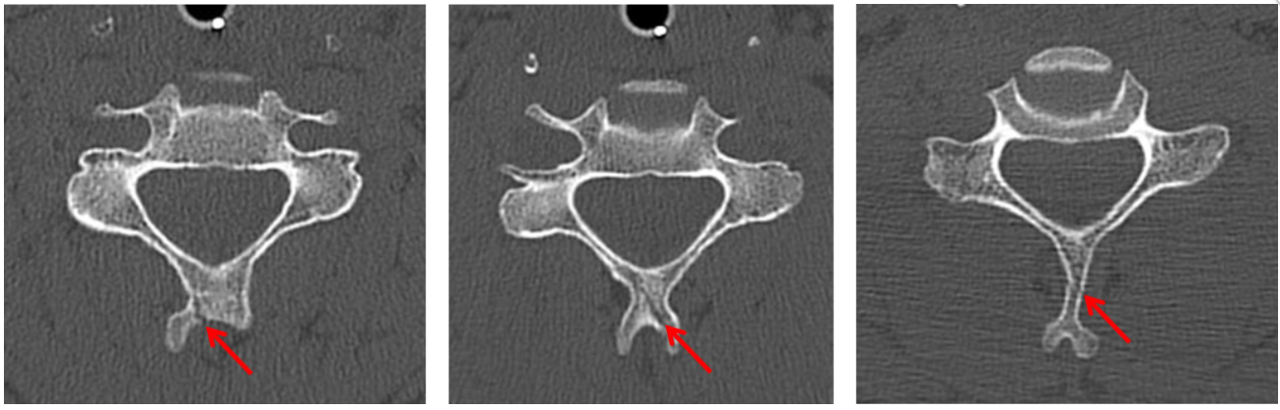

Red arrows: displaced left occipital condyle fracture.

Left C3 uncinate process fracture (red arrow).

Left C7 transverse process fracture (red arrow).

C4-C6 spinous process fractures (red arrows).